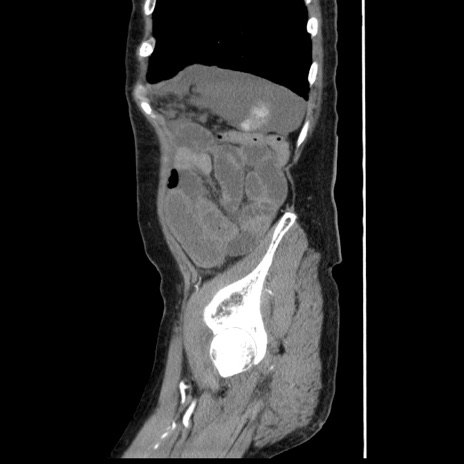

症例1(矢状断像)

【症例】80歳代女性

【主訴】腹痛

【現病歴】8時間前から腹痛あり来院。

【既往歴】糖尿病、脂質異常症、子宮体癌にて子宮全摘術

【身体所見】意識清明・会話良好だが腹痛で苦悶様、全腹部にわたって反跳痛と圧痛あり

【データ】WBC 13600、CRP 0.14、LDH 224、CK 90